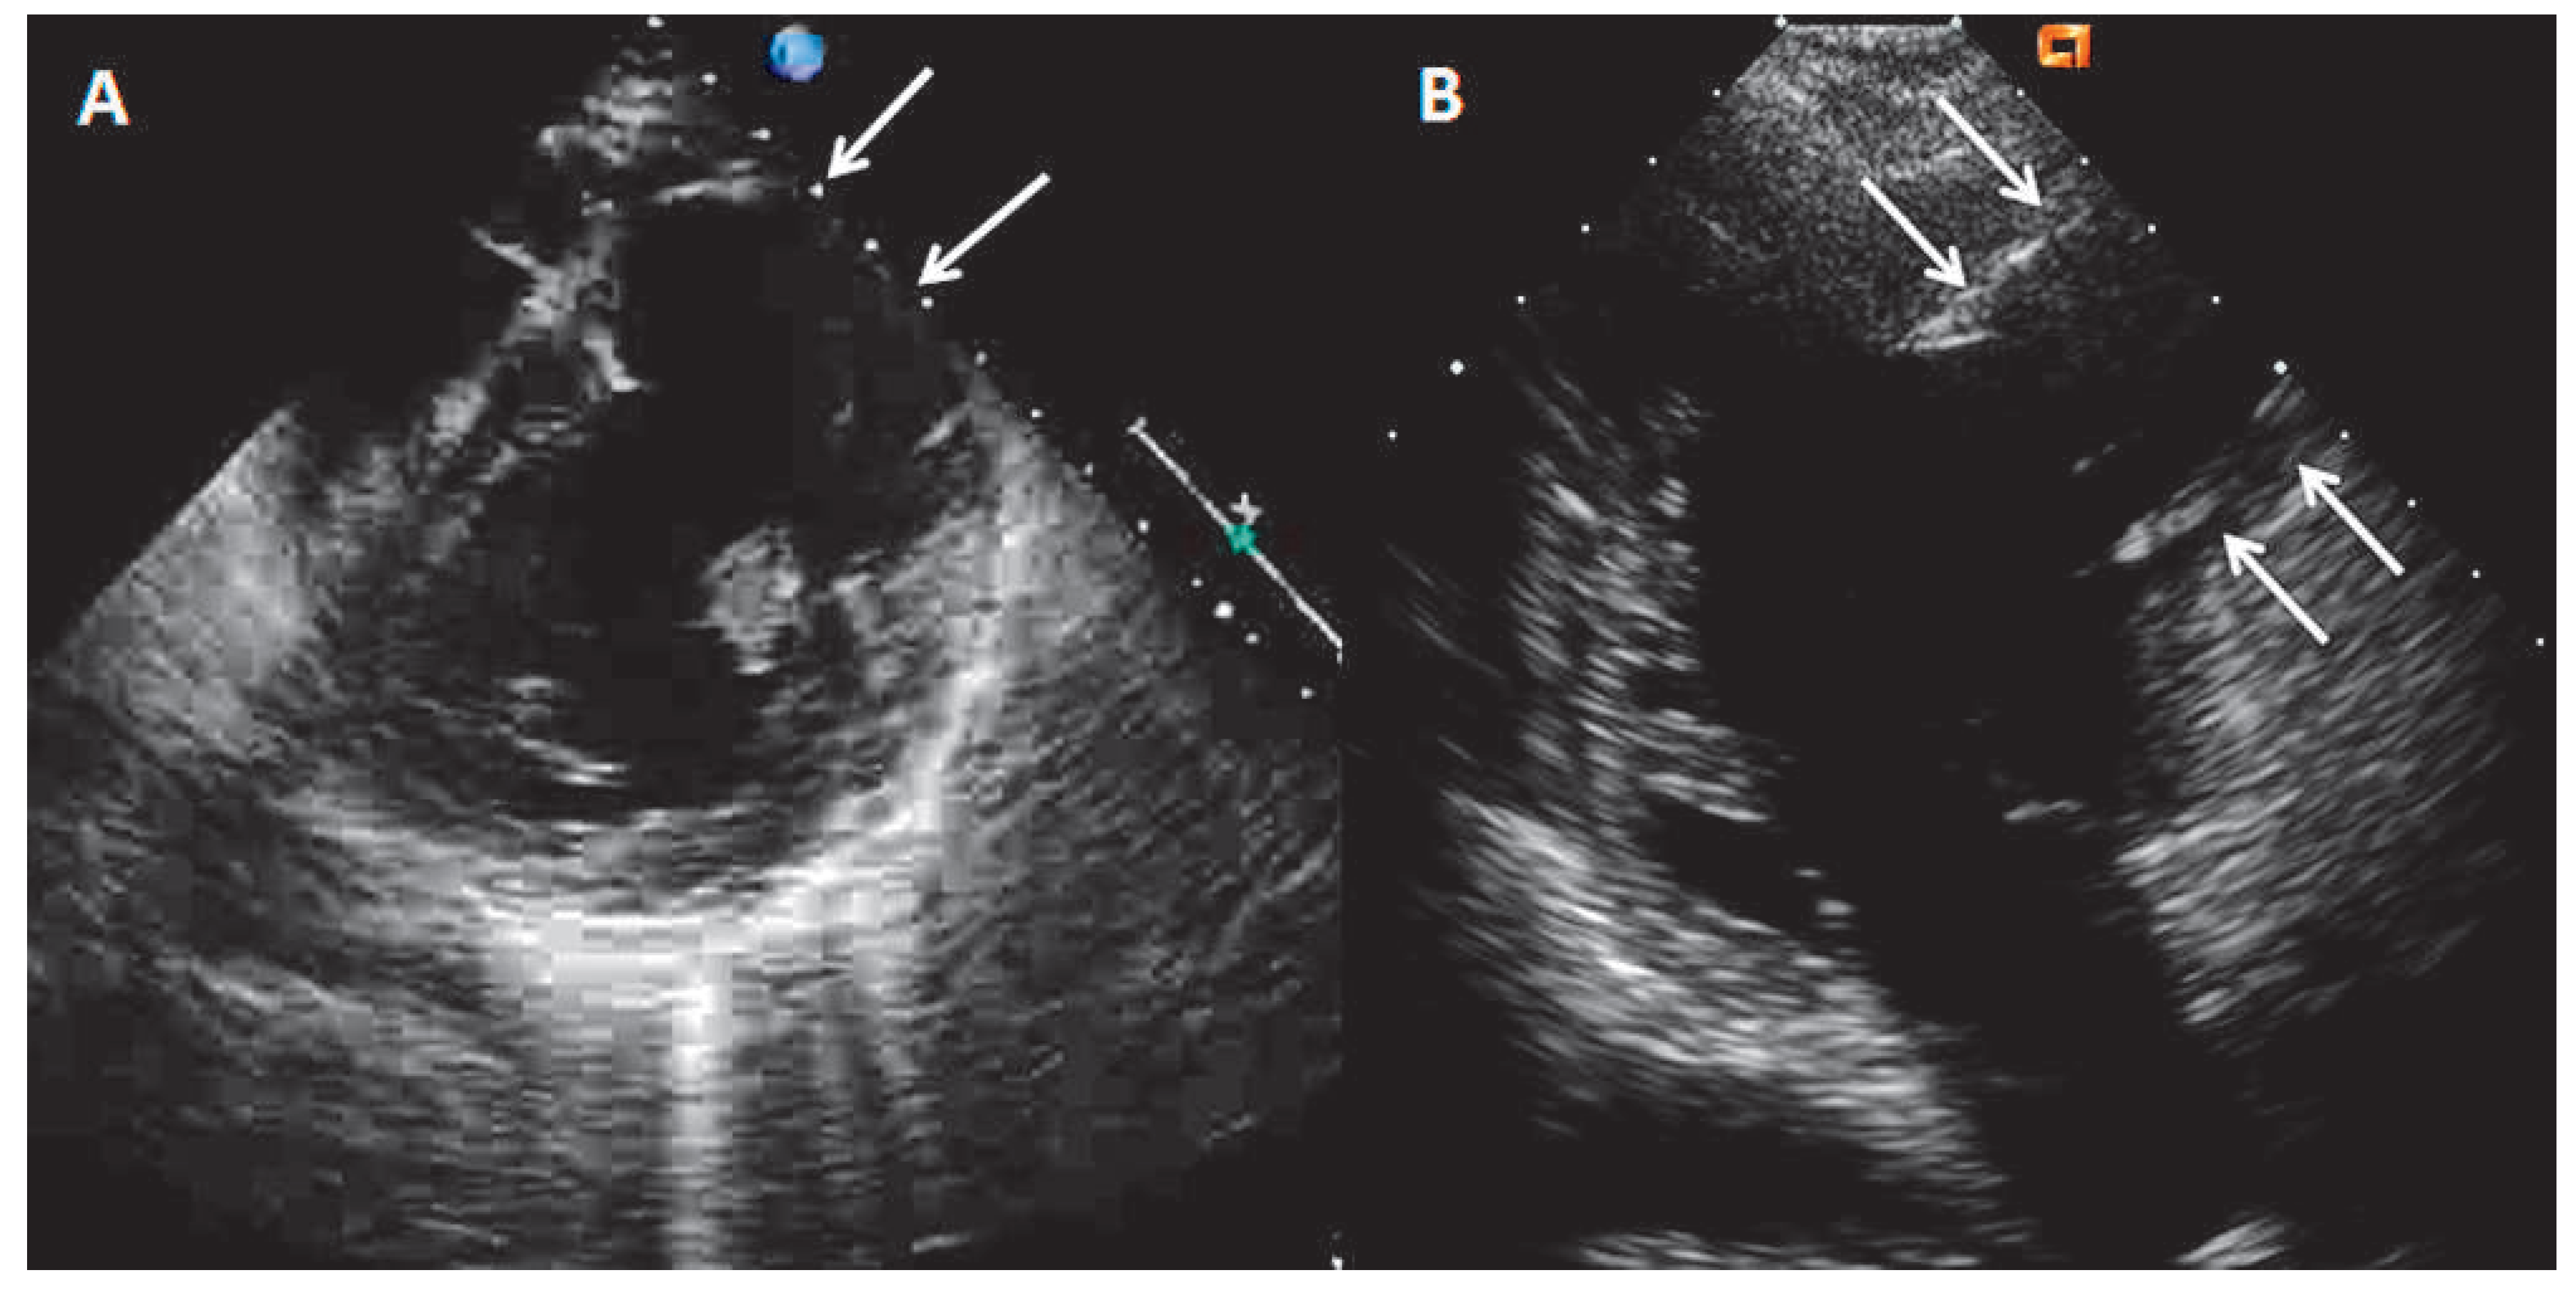

However, the patient’s recordings revealed that radiotherapy was performed in supraclavicular and axillary regions, without irradiation of mediastinum (Figure 4). According to the recordings the cumulative radiation dose was 47.5 Gy divided into 23 sessions. Another possible cause of LV bulging could be a diverticulum. However, its wall should contain endocardium, myocardium and pericardium and display normal contraction [2]. On the contrary in our case, MRI showed akynetic region with transmural LGE, which excludes the presence of normal myocardium and consistent with transmural scar. Cardiac sarcoidosis is another rare cause of aneurysm formation in the heart [3]. However, the previous serial PET investigations performed in the follow-up setting of the breast cancer never showed any pathological uptake either in the lungs or in the heart. From the old patient recordings we were able to recover the ECG of 2005 which showed the similar findings as the ECG on the index event.

Figure 4. The picture from the patient’s recordings from 1985 showing the region of radiotherapy application (arrows).